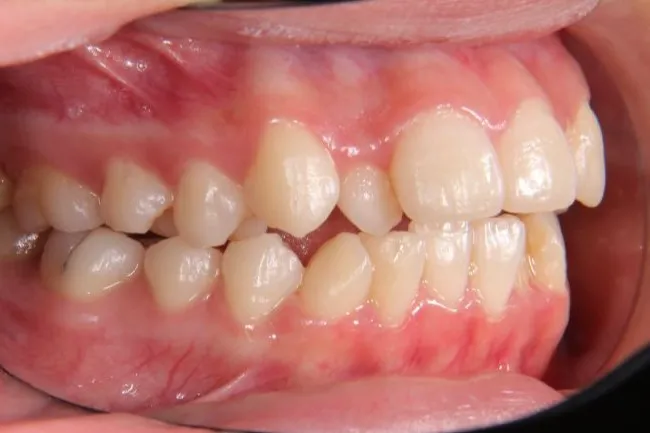

初診時年齢 高校生 (女性) 主訴 歯並びがガタガタ・口元の突出感

診断名 叢生・開咬・上下顎前突 装置名

特徴 ゆがんで生えている

状態 ガタガタ・でこぼこに生えている(叢生)

受け口(下顎前突/反対咬合)

前歯で噛めない(開咬/オープンバイト)

上下前歯、口元が出ている、口ゴボ(上下顎前突)

ガタガタの歯並びにお悩みの患者様でした。

口唇の突出感の他、下顎面高が長い印象も認められました。

歯科矯正アンカースクリューを用いた治療で、非抜歯で口唇突出の改善、臼歯の圧下、叢生の解消を図りました。

叢生は解消し、口元が大幅に引っ込み、下顎面高も縮小しました。